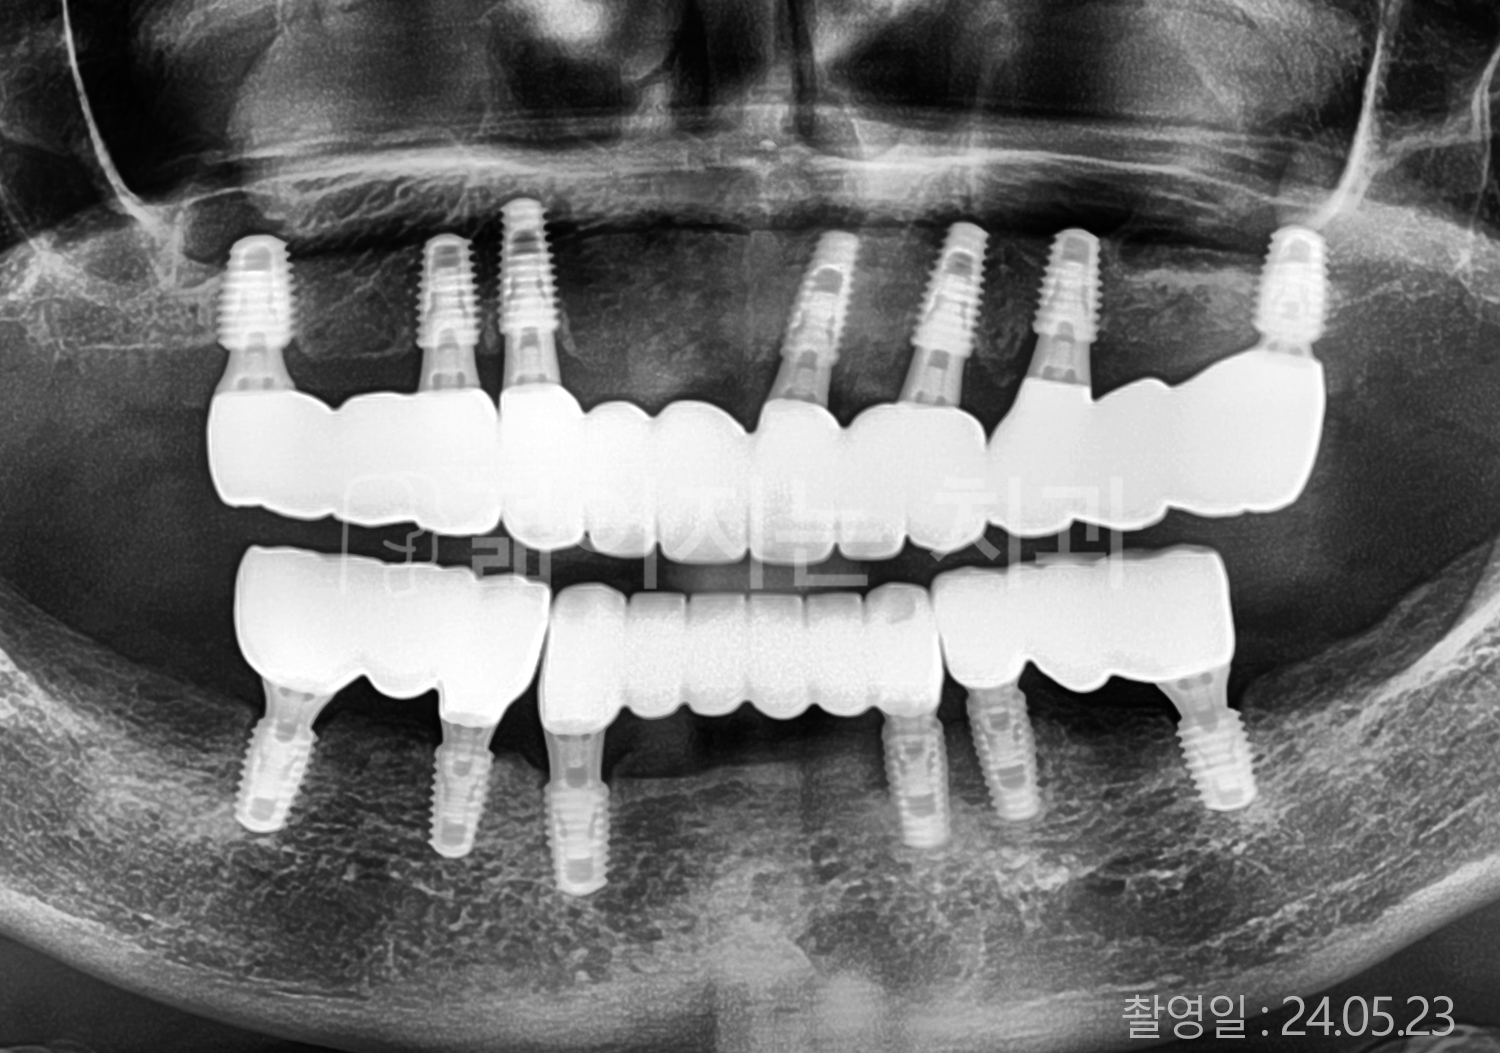

• 60대 고혈압, 고지혈증 전체치아 10개 이상 임플란트

• 70대 전체치아 10개 이상 임플란트

• 60대 전체치아 10개 이상 임플란트

• 50대 전체치아 10개 이상 임플란트

• 50대 고혈압, 고지혈증 전체치아 10개 이상 임플란트

• 60대 고혈압, 당뇨, 고지혈증 전체치아 10개 이상 임플란트

• 80대 고혈압, 당뇨, 골다공증 전체치아 10개 이상 임플란트

• 60대 고혈압 전체치아 10개 이상 임플란트

• 60대 고지혈증 전체치아 10개 이상 임플란트

• 60대 당뇨 전체치아 10개 이상 임플란트